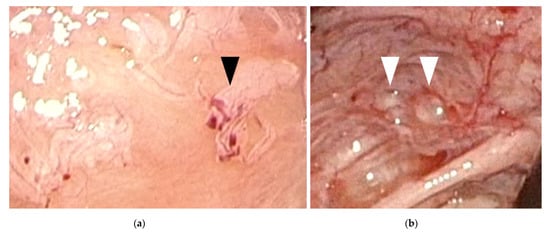

The findings of laparoscopic surgery are key factors in diagnosing endometriosis. Matalliotakis et al. reported that, during laparoscopic examinations, 45 out of 55 adolescent young girls (81.8%) were diagnosed with endometriosis stage I–II based on the revised American Society for Reproductive Medicine classification, while the remaining 10 (18.2%) were diagnosed as stage III–IV [24]. Audebert et al. reported similar results [27]. In general, ovarian endometriomas are frequently observed in women aged >20 years. “Powder-burn” lesions consisting of a mixture of black lesions and white scars, and “blueberry spots” referring to blue-black nodules, are typical peritoneal lesions that reflect chronic hemorrhage and fibrosis. In contrast, ovarian endometriomas are not frequently found in adolescents. Peritoneal lesions, especially red and clear peritoneal lesions (Figure 1a) and vesicular lesions (Figure 1b), which are characteristic of early-stage endometriosis, are the majority of lesions found in adolescents [7,28,29]. These superficial peritoneal lesions are reported to be highly inflammatory. Moreover, it has been shown that clear and red lesions are the most painful [30]. Early-stage lesions are difficult to detect even under laparoscopy. These microvascularizations and the filmy, free-floating adhesions on the peritoneal and ovarian surfaces collapse under pneumoperitoneum pressure. Laufer et al. reported that the conformation of these subtle lesions becomes easier to identify by filling the pelvis with normal saline, thereby distending the peritoneum and preventing collapse of lesions. Submersing the laparoscope under water to suppress light reflection also aids in identifying lesions [8,31]. The different findings detected in adults versus adolescents (adolescents primarily show early-stage lesions, whereas adults mainly show fibrosis and scarring) demonstrate that endometriosis is a progressive disease. When assessing and diagnosing endometriosis in adolescents, it is essential to direct careful attention to early-stage lesions, as these can be easily missed.

Figure 1.

Early-stage endometriosis lesions found in adolescents. (a) Red and clear peritoneal lesions on the peritoneum (black arrowhead); (b) Vesicular lesions (white arrowhead) found on the peritoneum near the left uterosacral ligament.